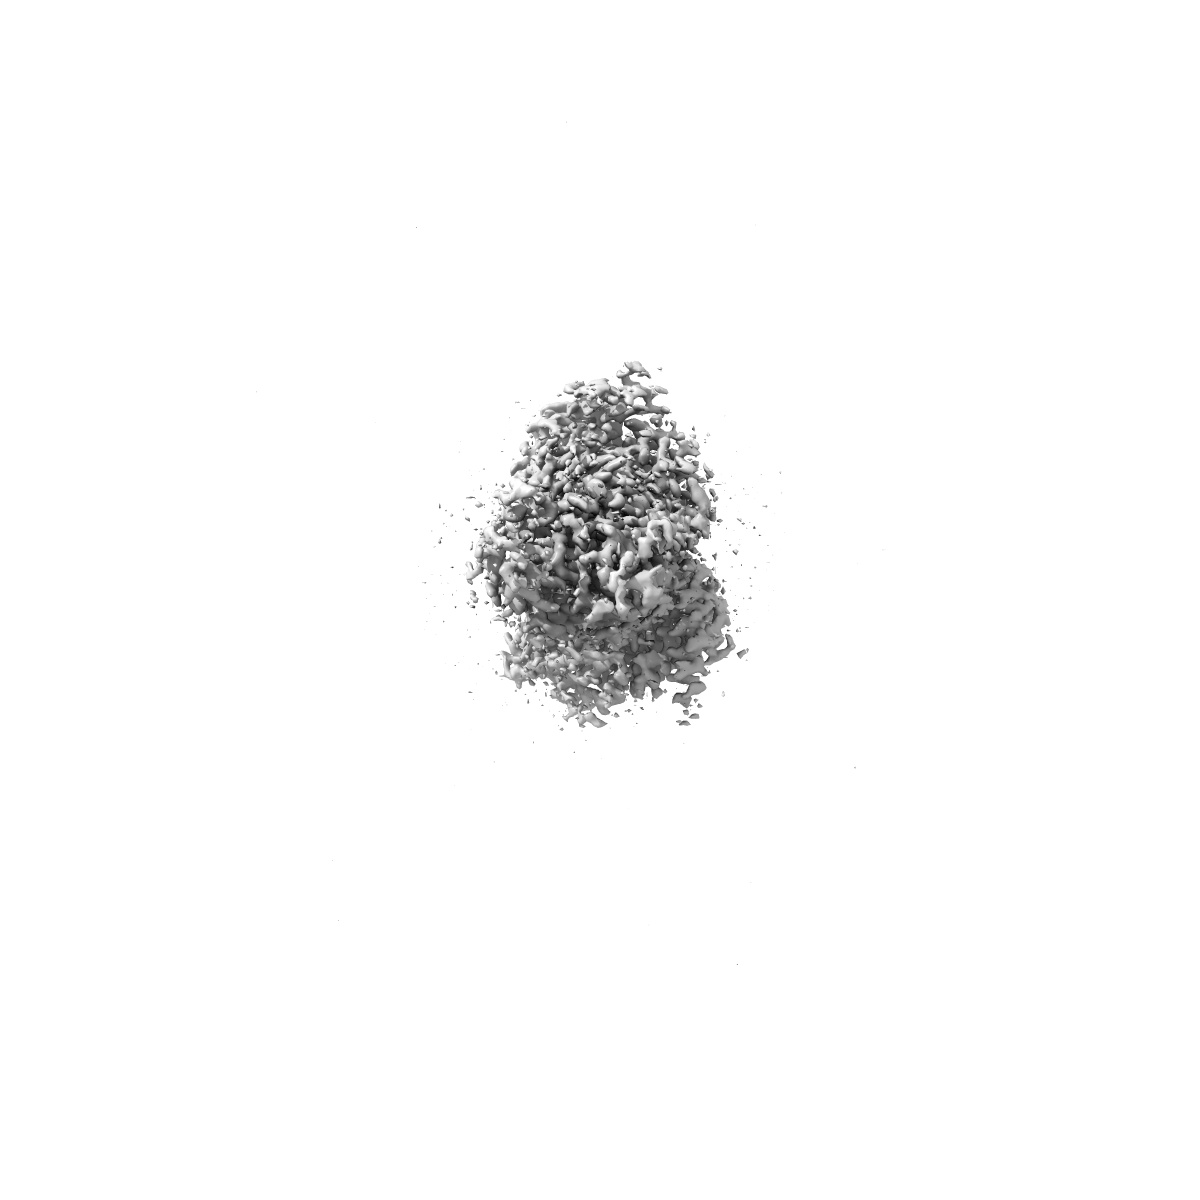

Human Amylin1 Receptor in complex with Gs and cagrilintide

Single-particle2.2 Å

Sample: Human Amylin1 Receptor in complex with Gs and cagrilintide

Structural and dynamic features of cagrilintide binding to calcitonin and amylin receptors.